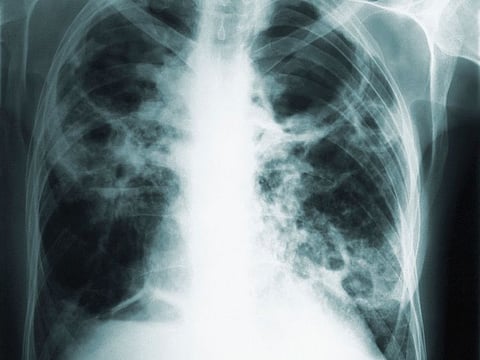

Tuberculosis patients suffer fevers and night sweats, lose weight, cough up blood and, if left treated, ultimately die. Five years ago, tuberculosis surpassed AIDS as the deadliest infectious disease worldwide.

BCG, which is not used in the United States, protects infants against some types of tuberculosis, but does not protect adolescents or adults against the form that attacks the lungs, which is the most common type.